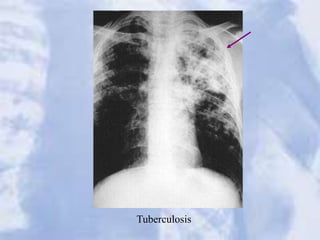

Tuberculosis